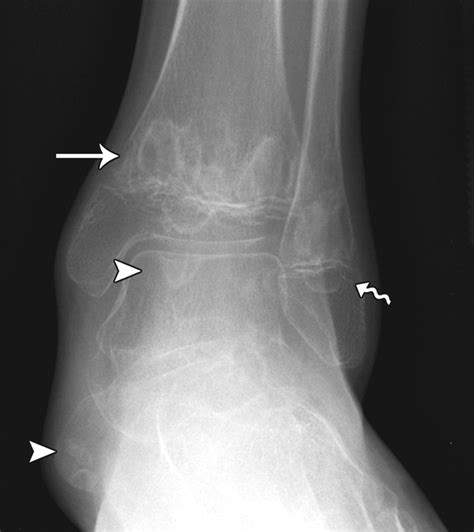

Diagnostic Approach and Imaging

Diagnosing Chronic Multifocal Osteomyelitis is a process of exclusion. Because there is no single laboratory blood test that confirms the diagnosis, physicians rely on a combination of clinical findings, imaging, and, in some cases, a bone biopsy to rule out other more serious conditions like malignancy or bacterial osteomyelitis.

X-rays Useful for evaluating bone damage, though often normal in the early stages.